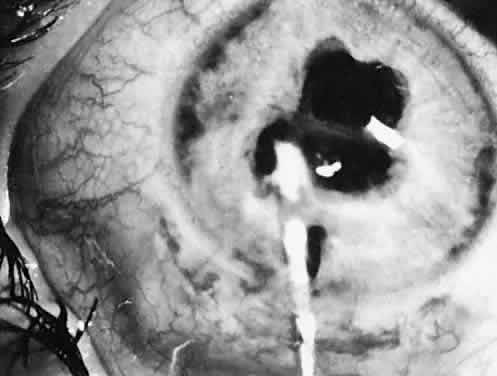

Usually, anterior polar cataracts are visually insignificant and allow normal visual development (see Fig. 1). However, some affect vision, and all require careful monitoring.7 Centrally located cataracts that are on or near the posterior lens capsule have a greater effect on the refraction of light and visual acuity (Fig. 2). Nuclear cataracts associated with metabolic disorders or prenatal infections produce double refracting systems that cause optical distortion and significantly decrease visual acuity (Fig. 3).